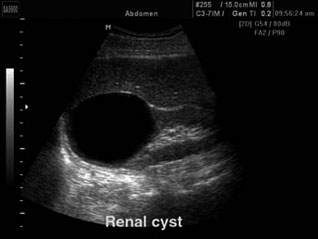

Parmi elles, nous citerons les tumeurs bénignes kystiques (kyste cortical simple et kyste parapyélique (cf Fig. 3) de grande fréquence, uniques ou multiples, ne nécessitant pas d'exploration complémentaire quand typiques, les tumeurs bénignes solides (angiomyolipome ou oncocytome).

Fig. 3